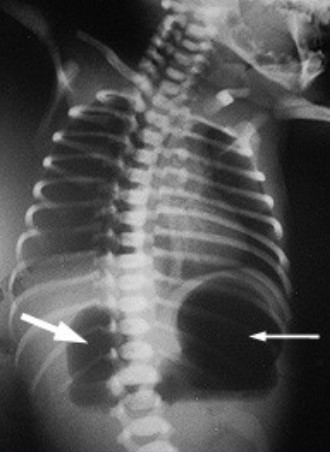

RECÉM NASCIDO, APRESENTOU VÔMITOS LOGO APÓS O NASCIMENTO. RSA DEMONSTROU ALÇAS DISTENDIDAS NO ABD SUPERIOR POR GASES (SINAL DA DUPLA BULHA). NO RESTANTE DO EXAME NÃO HAVIA ALTERAÇÕES. QUAL DIAGNÓSTICO?

Atresia Duodenal